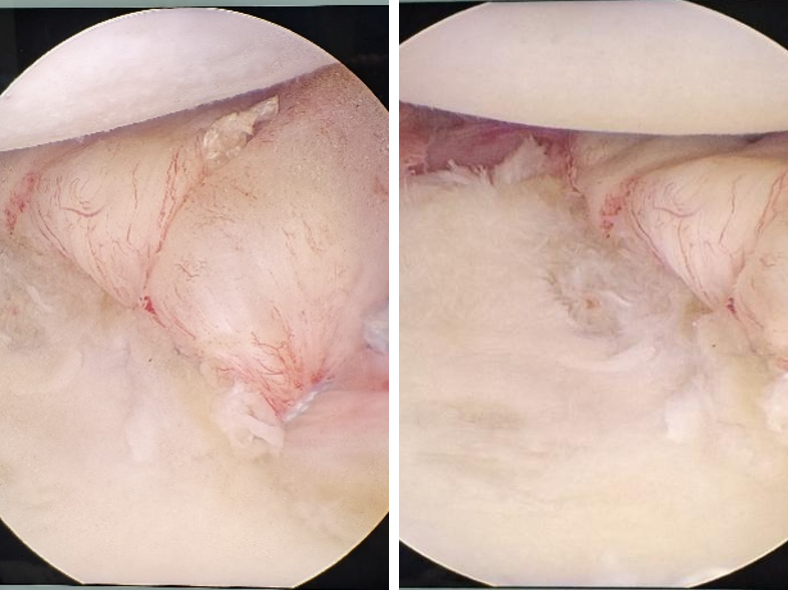

术中探查关节情况

关节镜下修补固定肩关节盂

关节镜下固定大结节骨块及修补肩袖